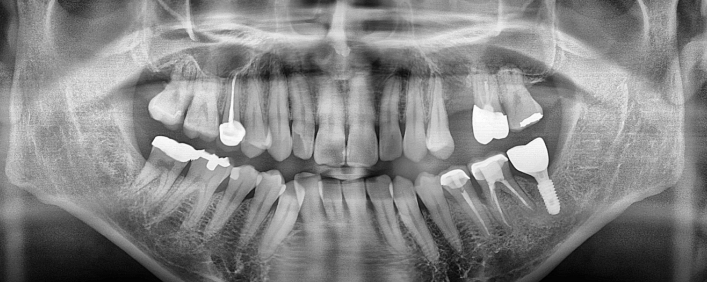

임플란트 치료사례

서울스마트치과는 결과로 증명합니다.

위 치료 사례는 서울스마트치과에서 직접 치료를 받고, 환자 본인의 동의를 얻어 게재된 사진으로 무단 인용, 도용, 재배포 시 민/형사상 책임을 질 수 있습니다.